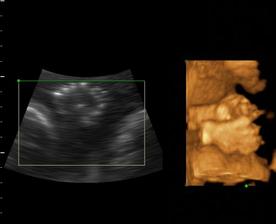

Naša maličká Emka alebo Silvinka...🙂

Od 19. júna 2008, teda od 21. týždňa vieme, že sa nám na 99% narodí dievčatko...na mene neodznela ešte úplná zhoda, preto Ema alebo Silvia...no ja dúfam, že sa mi podarí presadiť Emu, aj keď Silvia je tiež krásne meno...🙂...